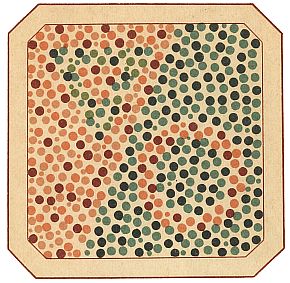

В настоящее время для испытания на цветовую слепоту применяются таблицы, где среди пятен одного цвета помещены пятна другого, составляющие вместе для всякого нормально зрячего какую-нибудь цифру, букву или фигуру. Цветнослепые не могут отличить цвет этих пятен от цвета пятен, служащих фоном, а следовательно, они не могут «прочесть» и соответствующих цифр, букв или фигур.

На рис. 1, помещенном на цветной вклейке, приведена испытательная таблица проф. Е. Б. Рабкина, на которой краснослепой — дальтоник не видит круга, а зеленослепой не видит треугольника. Цветовое зрение в современных условиях будет доставлять человеку все большее и большее наслаждение не только от восприятия прекрасного в природе и в живописи, но и в новых формах искусства — цветной фотографии и кино. Цвету придают все большее значение в промышленности, так как оказывается, что от правильно подобранной окраски производственных помещений и оборудования в значительной мере зависит производительность труда. Недалеко то время, когда приобретет массовое распространение цветное телевидение, а затем и цветомузыка.